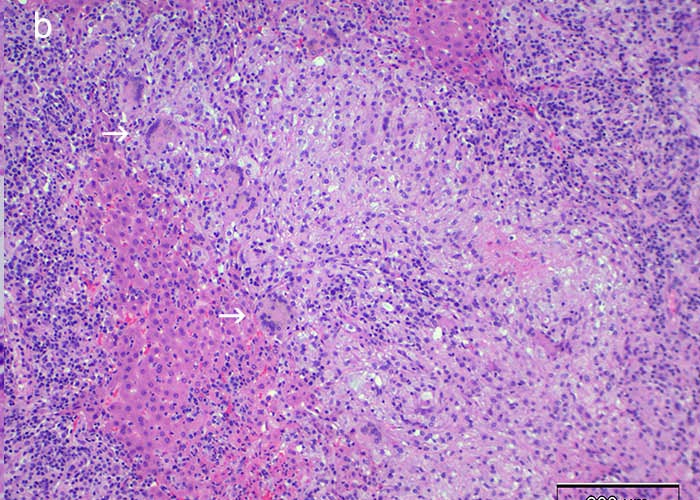

Histopathological lesions correspond to gross findings. Apoptosis of epithelial cells, particularly in suprabasilar stratified squamous epithelium, results in characteristic microvesiculation. This is seen in mucosa of the oral cavity, pharynx, larynx, oesophagus, forestomach and skin. While not unique to MCF, only a handful of infectious diseases in cattle and bison cause widespread microvesiculation, erosion and ulceration in epithelial mucosa and skin. Ulcerative enteritis and typhlocolitis are generally present. Urothelium appears to be a particular target of the dysregulated immune response of MCF. Degeneration, apoptosis and loss of urothelium in the renal pelvis, ureters, bladder and urethra is consistent, accompanied by lymphocytic-histiocytic inflammation (Figure 31).

Vascular lesions involve multiple organ systems, affecting arteries and veins. Veterinary pathology texts often illustrate the arteritis of MCF, since the thick lesioned walls of muscular arteries lend themselves to striking images. But phlebitis is equally widespread, albeit harder to identify.23 A pathologist who finds disseminated arteritis-phlebitis in tissues of cattle (Figure 32), bison and deer should consider MCF as a differential diagnosis. Examining the carotid rete (a rich vascular plexus surrounding the pituitary gland) (Figures 33 and 34), pampiniform plexus (intact males only) and/or vessels in the mesenteric stalk provides many appropriate-calibre veins and arteries for microscopic evaluation. Bison and deer tend to die of MCF after a shorter clinical course than cattle. This may explain why necrotizing medial arteritis, a useful hallmark of MCF in cattle, is less evident in those species.145,146,191,192 Deer with MCF sometimes have occlusive thrombosis with infarctions, a feature that is uncommon in bison and cattle.149

Lymphoid hyperplasia is generalized in lymph nodes of cattle, bison and cervid species that die of acute MCF. Some lymphocytes are large with lymphoblastoid features, but in more autolytic carcasses these can be hard to distinguish from reactive histiocytes. Similar lymphoblastoid cells are widespread in the inflammatory reaction of MCF, particularly in and around blood vessels. In lymph nodes they expand T-cell dependant areas. Multifocal degeneration of lymphocytes resulting in necrosis and oedema is common in lymph nodes, particularly in some cervid species. The inflammatory reaction of MCF around vessels is dominated by the presence of slightly atypical lymphocytes resembling or indistinguishable from macrophages. The typical infiltrate comprises lymphocytes, histiocytes-macrophages, plasmacytes, and neutrophils.

Disease due to CpHV-2 in sika deer can be associated with severe alopecic clinical dermatitis. In addition to necrotizing lymphocytic vasculitis, cutaneous lesions may be florid and granulomatous, with giant cell infiltration and mural folliculitis.35 Generalized vasculitis in non-cutaneous tissues may be granulomatous, although this is not invariable. It is unclear whether the chronic lesions associated with prolonged survival that are associated with CpHV-2 in some cervids reflect inherently lower viral pathogenicity relative to OvHV-2 or AlHV-1, or is a peculiarity of sika deer. OvHV-2 in experimentally-challenged rabbits causes a granulomatous response, generally within three weeks of challenge, most commonly in portal areas of the liver and, in some, is associated with widespread hepatic necrosis (Figures 35 a and b).

Figure 35 a Variation in nature of inflammatory reaction due OvHV-2, determined by species. Typical lymphohistiocytic reaction restricted to portal area of liver in a bull dying of MCF. (Courtesy of D O’Toole, Department of Veterinary Sciences, 1174 Snowy Range Road, Laramie, Wyoming, USA, 82070)

Figure 35 b Granulomatous portal-periportal hepatitis due to OvHV-2 in rabbit following challenge. Note numerous giant cells (arrows) and considerably more florid inflammation reaction involving periportal areas (Courtesy of D O’Toole, Department of Veterinary Sciences, 1174 Snowy Range Road, Laramie, Wyoming, USA, 82070)